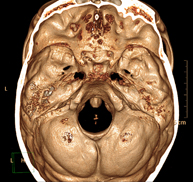

- TC Crani

Prova radiològica que consisteix en obtenir imatges del crani d'alta definició anatòmica (tronc cerebral, cerebel, cervell, calota cranial, etc. ) mitjançant l'ús d'un equip de TC (Tomografia Computeritzada). Indicacions: traumatismes, cefalea, trastorns de la memòria, pèrdua de força sobtada en una extremitat o meitat del cos. - TC Coll